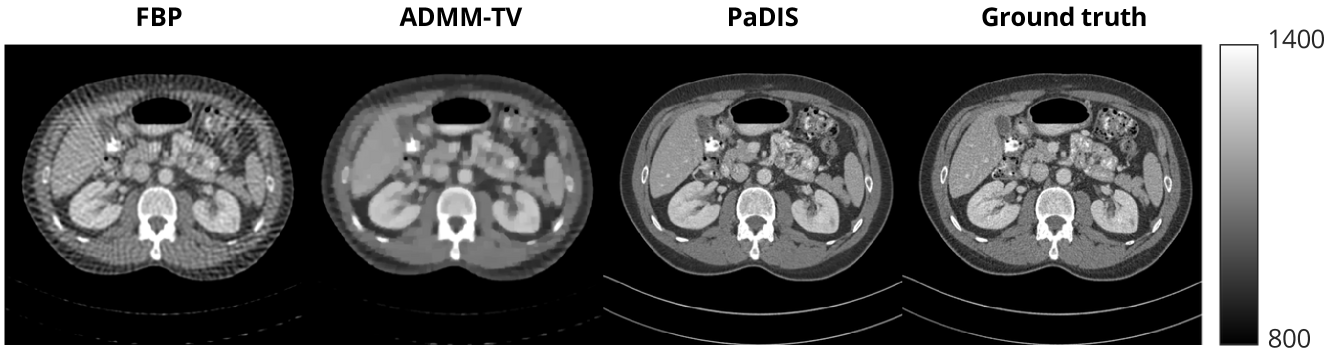

We tested the proposed method on a variety of different inverse problems: CT reconstruction, deblurring, and superresolution. For the forward and backward projectors in CT reconstruction, we used the implementation provided by [ODL]. We performed two sparse view CT (SVCT) experiments: one using 8 projection views, and one using 20 projection views. Both of these were done using a parallel-beam forward projector where the detector size was 512 pixels. For the deblurring experiments, we used a uniform blur kernel of size 9×9999\times 99 × 9 and added white Gaussian noise with σ=0.01𝜎0.01\sigma=0.01italic_σ = 0.01 where the clean image was scaled between 0 and 1. For the superresolution experiments, we used a scaling factor of 4 with downsampling by averaging and added white Gaussian noise with σ=0.01𝜎0.01\sigma=0.01italic_σ = 0.01. DPS has shown to benefit significantly from using a higher number of neural function evaluations (NFEs) [chung:23:dps], so we use 1000 NFEs for all of the diffusion model experiments. Appendix A.7 discusses this further.

For the comparison methods, we trained a diffusion model on entire images using the same denoising score matching method shown in Section 3.1. The inference process was identical to that of the patch-based method, with the exception that the score function of the image at each iteration was computed directly using the neural network, as opposed to needing to break up the zero-padded image into patches. We also compared with two traditional methods: applying a simple baseline and reconstructing via the total variation regularizer (ADMM-TV). For CT, the baseline was obtained by applying the filtered back-projection method to the measurement 𝒚𝒚\bm{y}bold_italic_y. For deblurring, the baseline was simply equal to the blurred image. For superresolution, the baseline was obtained by upsampling the low resolution image and using nearest neighbor interpolation. The implementation of ADMM-TV can be found in [Hong_2024]. We also implemented two plug and play (PnP) methods: PnP-ADMM [xiaojian11] and regularization by denoising (RED) [xiaojian6]. We trained denoising CNNs on each of the datasets following [Ronneberger2015UNetCN] and then used them to solve the inverse problems.

Table 1 shows the main inverse problem solving results. The best results were obtained after training the patch-based models for around 12 hours, while the whole image models needed to be trained for 24-36 hours, demonstrating a significant improvement in training time. Furthermore, when averaging the metrics across the test dataset, our proposed method outperformed the whole image method in terms of PSNR and SSIM for all the inverse problems. The score functions of all the patches can be computed in parallel for each iteration, so the reconstruction times for these methods were very similar (both around 5 minutes per image). The whole-image results could be more favorable if more training data were used. See data-size study in App. A.3.

Figure 5: Results of CT reconstruction. 60 views are used for the top two rows, 20 views are used for the bottom two rows. To better show contrast between organs, we use modified Hounsfield units (HU) in the top figure, while we use the same scale the images were trained on in the bottom figure.

In the bottom of Figure 5, some artifacts are present in the reconstructions obtained by the diffusion model methods, although they are more apparent in the whole image model than with PaDIS. The measurements are very compressed in this case, so it is very difficult for any model to obtain diagnostic-quality reconstructions; the baselines perform significantly worse in terms of quantitative metrics and exhibit severe blurring. In clinical settings, patient diagnosis are typically performed with CT scans consisting of hundreds of views. The top of Figure 5 shows that when 60 views are used, our proposed method yields a much better reconstruction without artifacts. Nevertheless, we show the potential of our proposed methods to reconstruct images from very sparse views with a decent image quality, which could be potentially used for applications such as patient positioning.